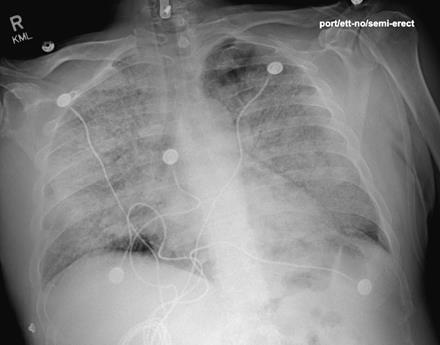

The right hallux wound (approximately 1.5 cm x 2.0 cm) had purulent, dishwater-like drainage with malodor, crepitus, and proximal spreading cellulitis with streaking. Clinically, the wound probed deeply to the underlying bone. The patient denied allergies to medication, food, or other products. The patient had no previous history of smoking. We started empiric vancomycin and piperacillin-tazobactam antibiotics for broad-spectrum Gram-positive and Gram-negative aerobic and anaerobic coverage. X-rays of the right foot revealed gas in the first interspace of the right foot with concern for osteomyelitis of the base of the second proximal phalanx. A preoperative chest X-ray (see image to left) showed no interstitial edema or pneumothorax, and EKG demonstrated sinus tachycardia. The patient underwent an emergent incision and drainage of the right foot, tolerating the procedure and anesthesia well without apparent complications. Multi-team based staged approach was utilized to attempt limb salvage with definitive right foot trans-metatarsal amputation (TMA) to follow once achieving resolution of the gaseous infection.